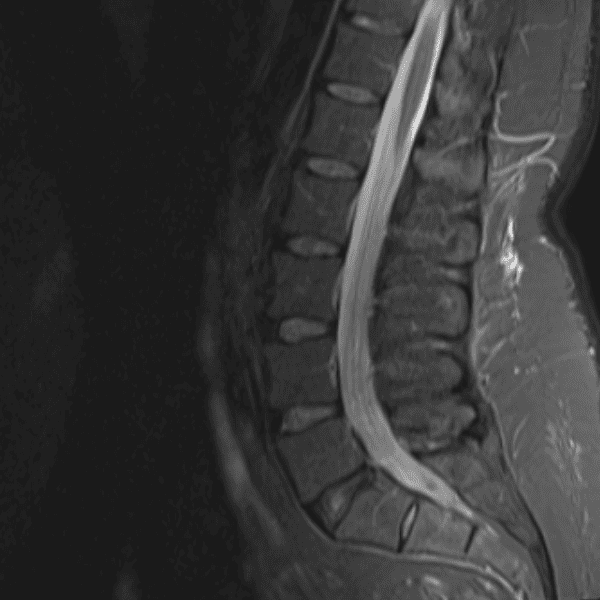

Simulates call by including subtle or difficult cases and some normals.

35 cases